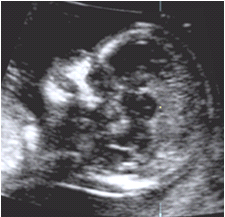

Diagnóstico ultrassonográfico:

- Dilatação uni ou bilateral dos ventrículos laterais cerebrais no corte transverso cerebral.

- Subdividido de acordo com o diâmetro do ventrículo lateral em leve (10-12mm), moderada (13-15mm) e severa (>15mm).